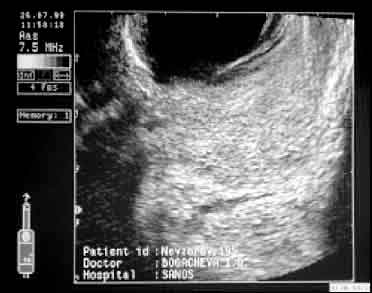

| ТРУЗИ простаты больного Н., 1956 г.р. до лечения, продольное сканирование (а). В правой доле простаты на фоне неравномерного понижения эхогенности ткани больше по вентральной поверхности определяются микрополости неправильной формы (микроабсцессы). | То же после 15-дневного курса дренирующей терапии (б). Микрополости исчезли, эхогенность и структура ткани полностью восстановились. |